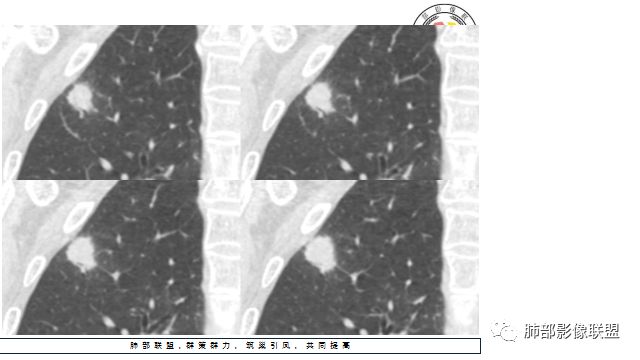

2.右肺尖类圆形结节影,边界清楚,未见明显分叶或深切迹,部分分边缘较平直,可见细长毛刺棘状突起,相邻胸膜增厚,未见胸膜凹陷。后段胸膜下见条索影及微小结节影。

相关血管未见脐凹,有限图像层面未能显示相关支气管情况。

3.平扫病灶密度密度不甚均匀,外侧份见微小高密度影。

4.增强扫描成明显环形强化,中央液化坏死,内壁清楚且较为规整。